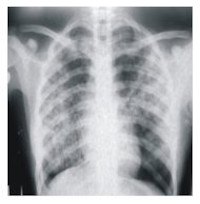

Radiological Assessment Of Lateral Chest Wall Soft Tissue Thickness In Pulmonary Tuberculosis

Rationale: Weight loss is one of the many symptoms of pulmonary tuberculosis. It can also be found in other wasting diseases like malnutrition, malignancies and HIV infection and AIDS. As a result of this, it is expected that there will be a reduction in the soft tissue thickness of the lateral chest wall in patients with pulmonary tuberculosis and subsequent increase, when treatment has been adequately effected.

Objective: The purpose of this study is to find out if there is any definite reduction in the soft tissue thickness of patients with pulmonary tuberculosis when compared with healthy controls.

Methods: This is a prospective study in which the lateral chest wall soft tissue thickness on chest radiographs of 203 patients (children & adults) with bacteriologically and radiologically proven pulmonary tuberculosis, and nine months post-treatment asymptomatic and bacteriologically negative cases were measured. These were compared with a control group of 50 well-nourished patients, age and sex-matched and who had no clinical and radiological features of pulmonary tuberculosis.

Results: The total mean values of the subcutaneous fat and muscle layer thickness of the pre-treatment tuberculosis cases were 6.89 + 2.6mm and 8.13±2.85mm respectively. The mean values of the subcutaneous fat laver were observed to be significantly lower than the muscle layer in all the age groups (P<0.05). The mean subcutaneous fat and muscle layer thickness of the post-treatment cases were 14.47±6.09mm and 10.73+3.36mm respectively. A significant (P<0.05) increase in thickness was observed in the subcutaneous fat laver over that of the muscle layer in the post-treatment phase. The total mean values of subcutaneous fat and muscle layer thickness in the control group were found to be 16.4 ± 5.6mm and 9.8 2.9mm respectively. The fat layer recorded higher values than the muscle laver. In all, the total mean soft tissue thickness (14.7+5.2)mm in the pre-treatment tuberculosis patients was significantly (P<0.05) lower than in the post treatment (25.2+8.55)mm and control (26.247.6mm).

Conclusions: The clinical implication of this study is that the total soft tissue thickness of the lateral chest wall can be used as an index for monitoring recovery in patients with pulmonary tuberculosis during treatment